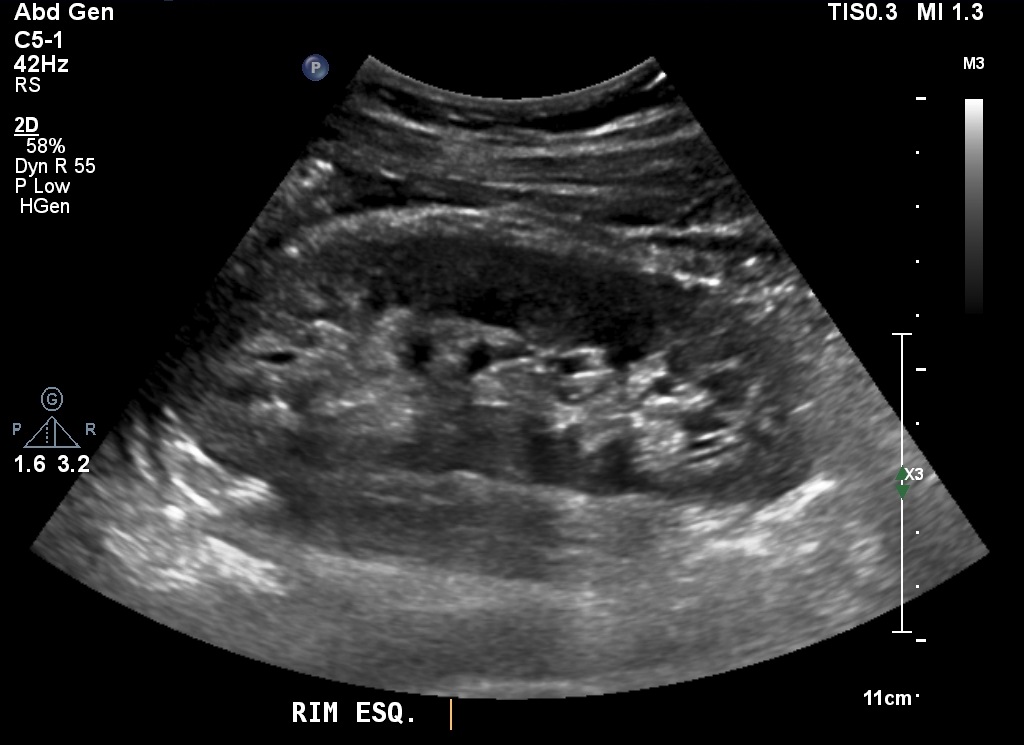

Adolescente de 16 anos veio ao laboratório para fazer ultrassonografia abdominal e escrotal, embora não tivesse queixas clínicas ou alterações evidentes ao exame físico. Estava em acompanhamento laboratorial de proteinúria leve e albuminúria havia seis anos, sem causa esclarecida. Os valores de proteinúria variavam entre 0,21 e 0,68 g/L (VN inferior a 0,05 g/L) e 0,16 e 1 g/24h (VN inferior a 0,15 g/24h). Já os de albuminúria variavam entre 32 e 545 g/24h (VN inferior a 0,15 g/24h). Os demais exames laboratoriais de sangue e urina encontravam-se dentro da normalidade.

As imagens da ultrassonografia abdominal avaliaram o rim esquerdo (A) e a veia renal esquerda no eixo longo (B). Ao estudo com Doppler colorido e pulsado, a veia renal esquerda foi visualizada ao longo do seu trajeto (C) e as velocidades, aferidas na sua porção proximal (D). A ultrassonografia escrotal com Doppler, em repouso, mostrou o fluxo das veias do plexo pampiniforme esquerdo (E)